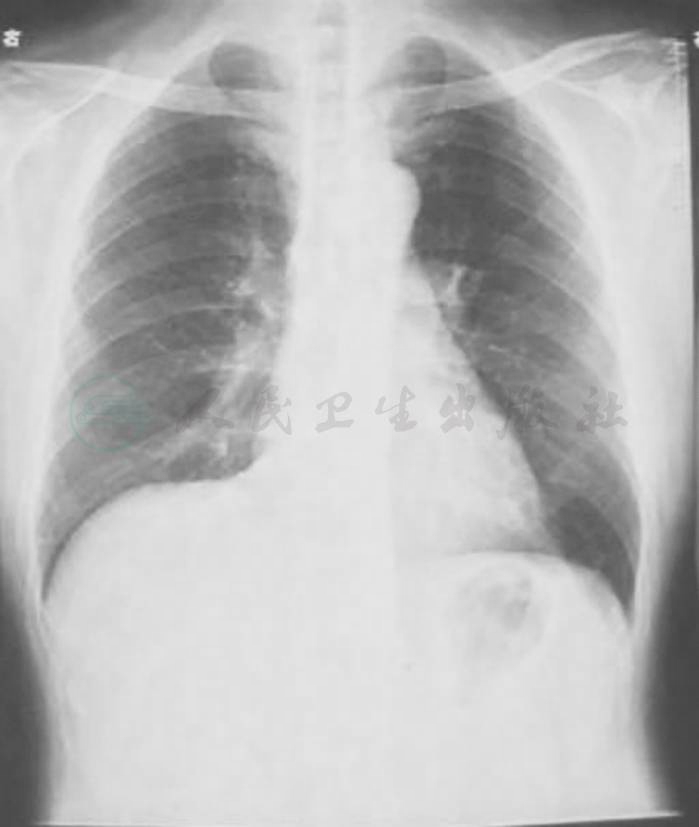

图1 X线胸片(2009-11-04)

X线胸片示左下叶斑片影,右上肺纹理增多